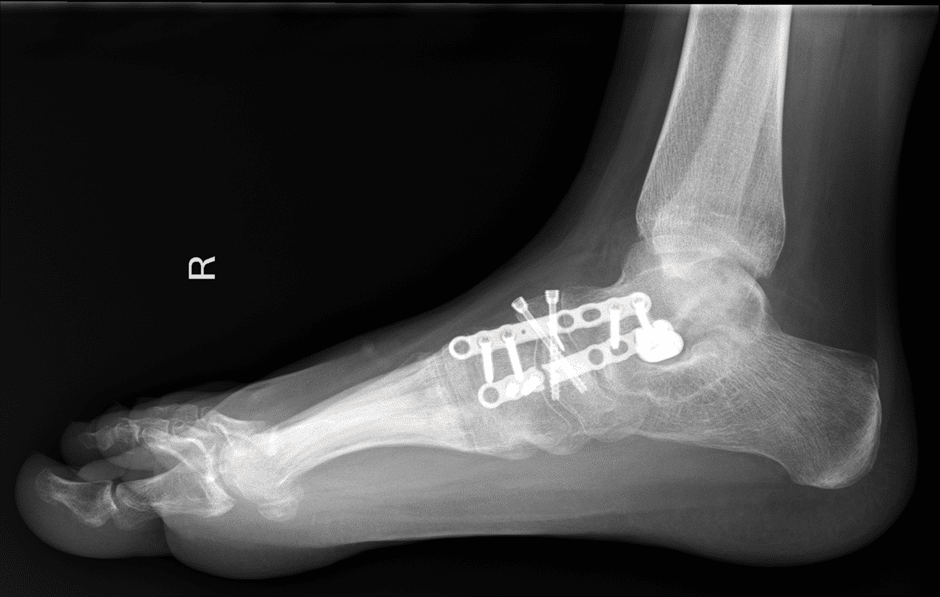

Tarsal scaphoiditis Kohler disease saggital xray of the foot of a Kohler's Disease Foot Kohler disease is most commonly seen in males ages 4 to 7 years old. The symptoms include pain, swelling, and difficulty walking. Kohler disease is a rare condition that affects the foot bones in children. Kohler's disease is a rare idiopathic condition caused by avascular necrosis of the navicular bone that occurs in young children and. Kohler’s disease is a. Kohler's Disease Foot.